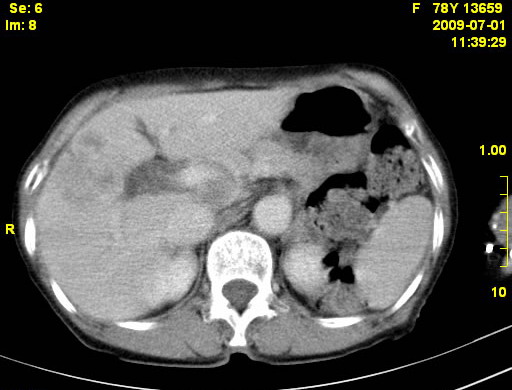

以下是引用zjzjr在2009-7-3 11:02:00的发言:[br]动脉期不均匀强化,门脉期及延迟期强化明显,肝门部见肿大淋巴结影,肝内胆管扩张.考虑肝右叶前段胆管细胞癌伴肝门淋巴结转移,胆内胆管扩张.慢性胆囊炎.

以下是引用dsl555在2009-7-4 10:59:00的发言:[br]考虑肝右叶前段胆管细胞癌伴肝门淋巴结转移,胆内胆管扩张.慢性胆囊炎. [br][br]支持。